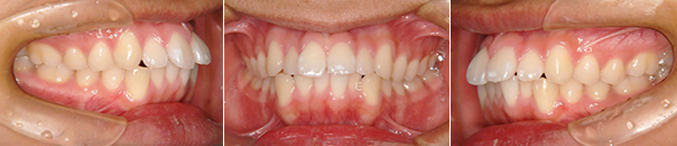

症例:上顎と下顎を拡げて治療した症例

治療前

症状:前歯部叢生(前歯のガタガタ)

初診時年齢:7歳8ヶ月

治療期間:1期治療で拡大装置を2年3か月使用。2期治療でマルチブラケット装置を2年1か月使用。

治療費:1期治療費 30万円+毎回の調節料(税別)/2期治療費 35万円(セラミックブラケット)+毎回の調節料(税別)

副作用とリスク:歯を移動すると幾分か歯根が吸収されて短くなることがあります。特に生活に支障がない場合が殆どです。

治療終了

正しい咬み合わせが獲得できました。